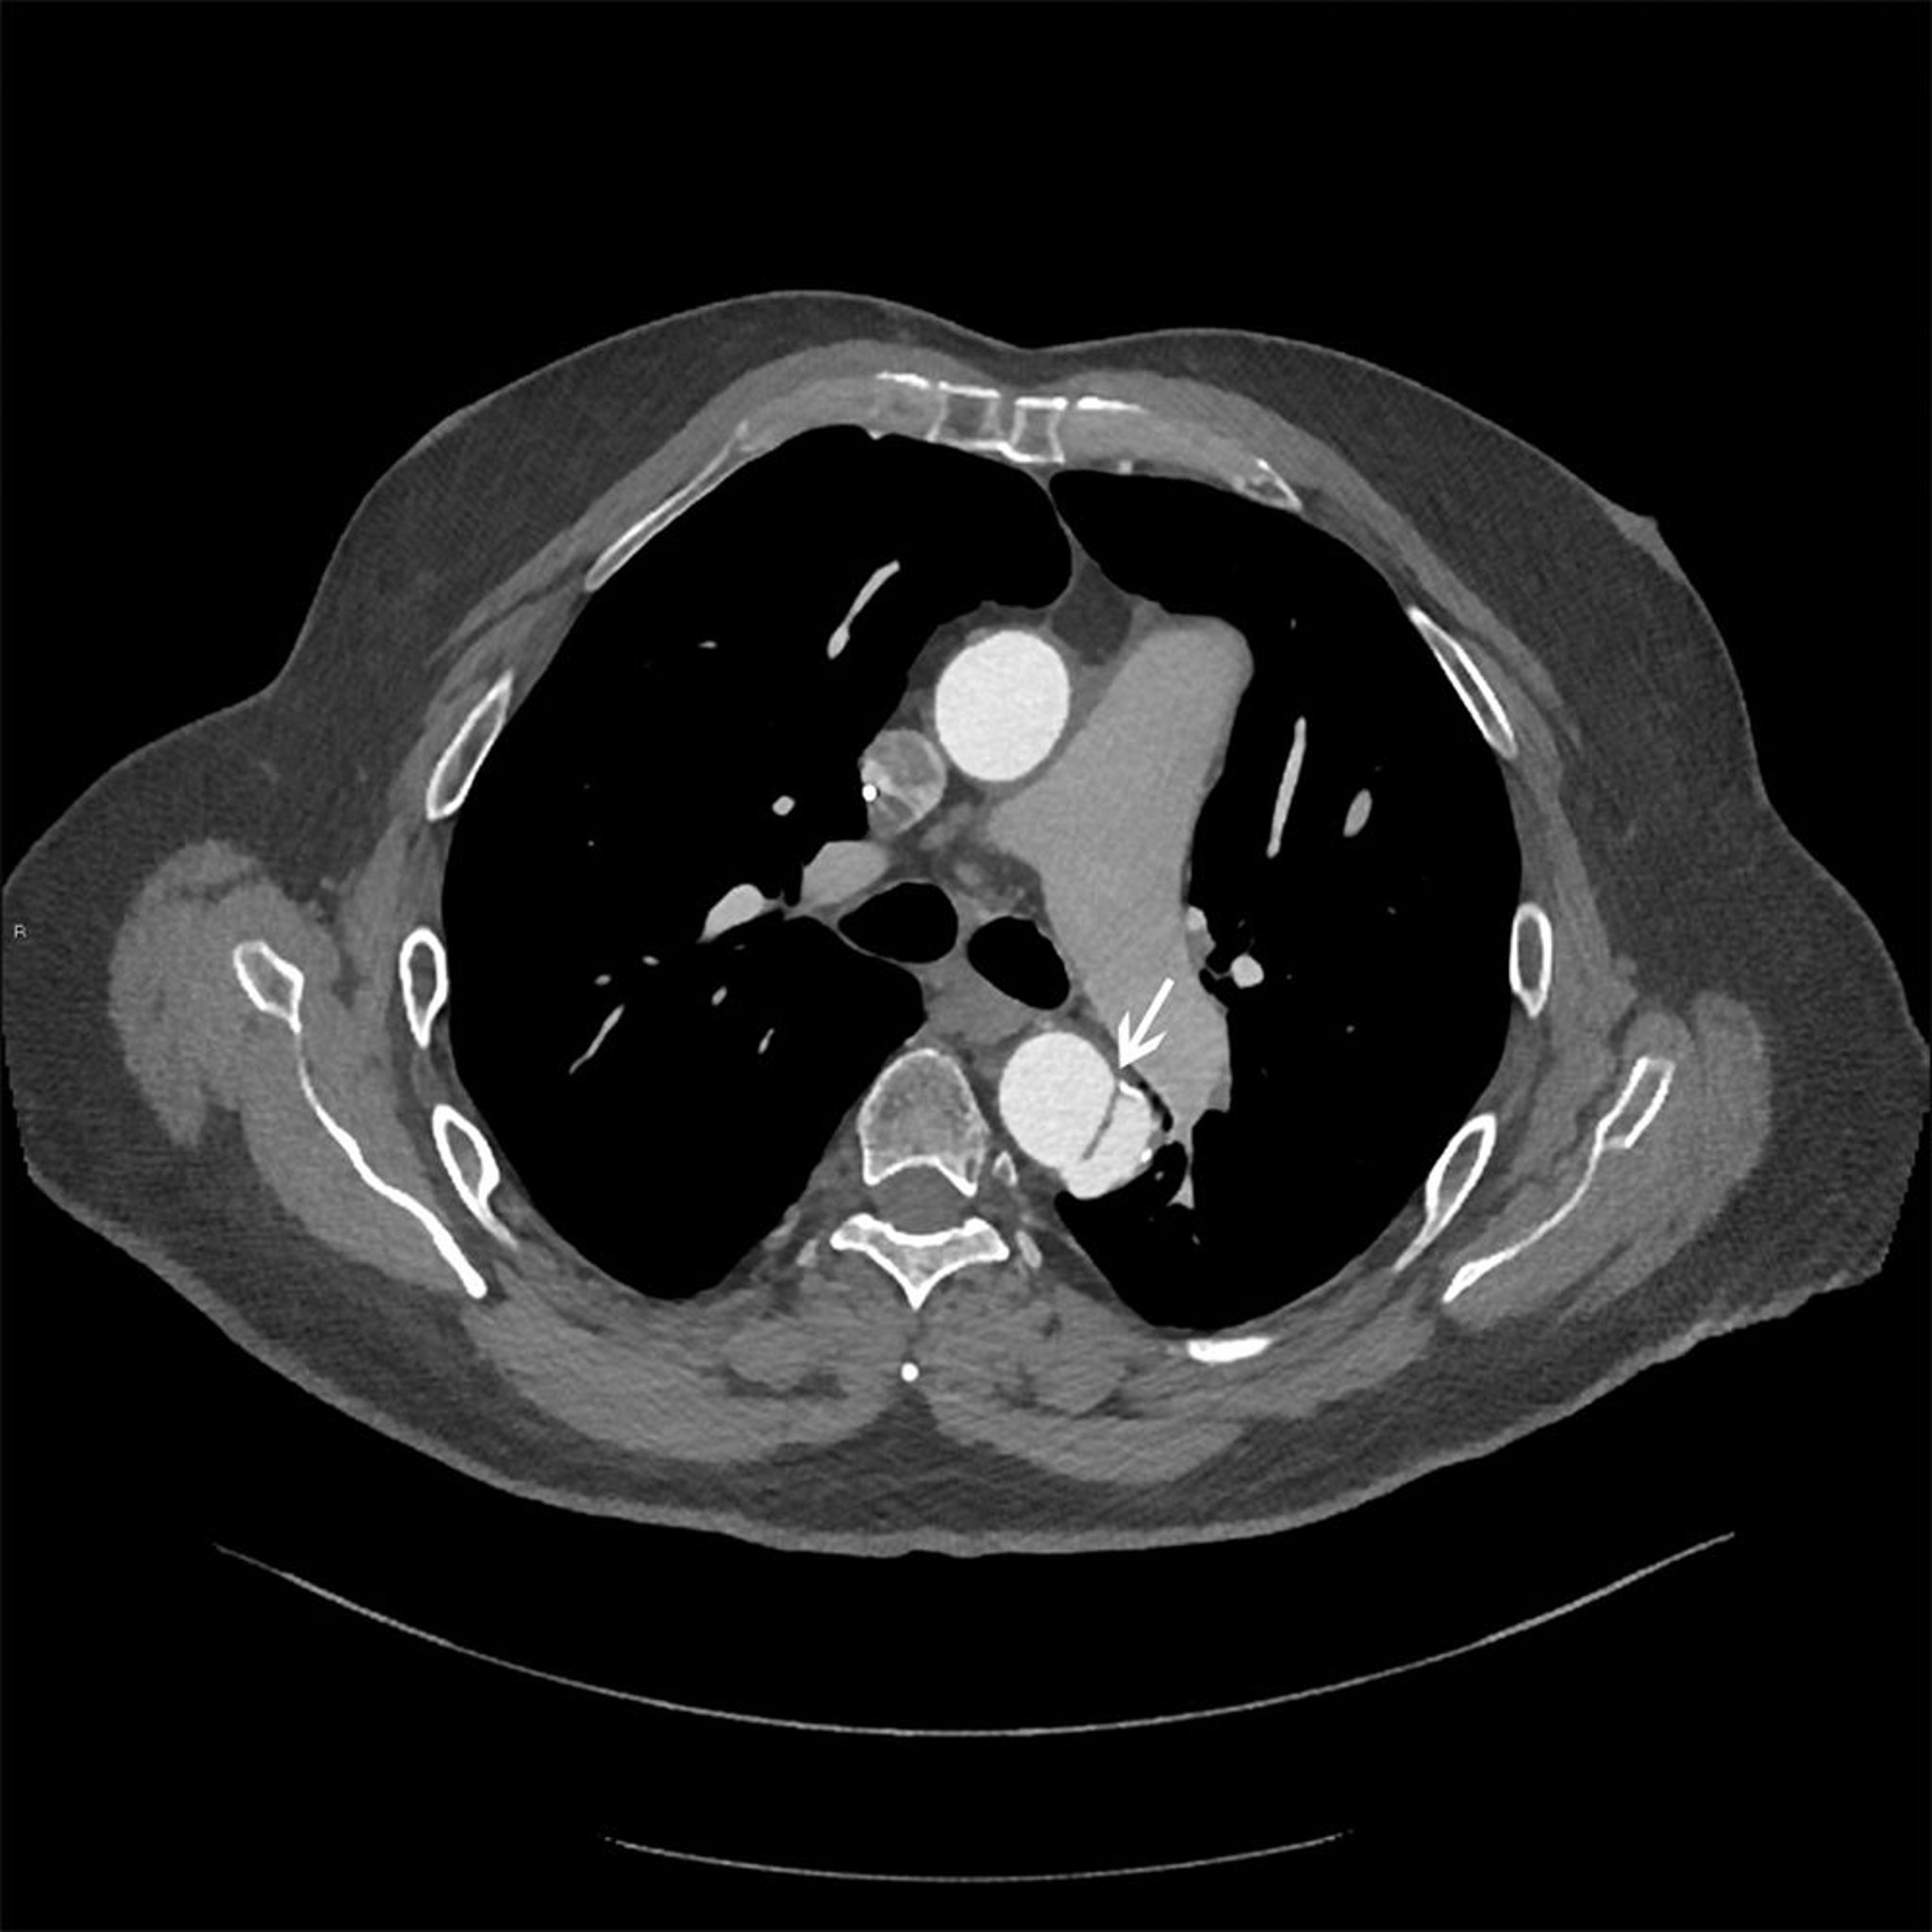

胸部大動脈解離(Stanford B型)

下行大動脈の解離したフラップ(白矢印)の水平断像。

© 2017 Elliot K.Fishman, MD.